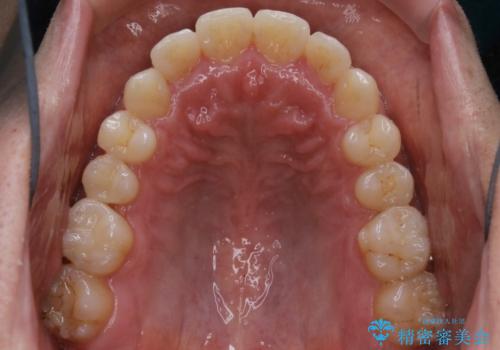

- 上下の前歯のがたつきが気になるとご相談にいらした方です。光加速矯正装置(オルソパルス)を用いて短期間で仕上げることが出来ました。

一般的に噛む力が強い方は矯正治療に時間がかかると言われてます。光加速矯正装置(オルソパルス)を用いることで短期間で仕上げることができました。